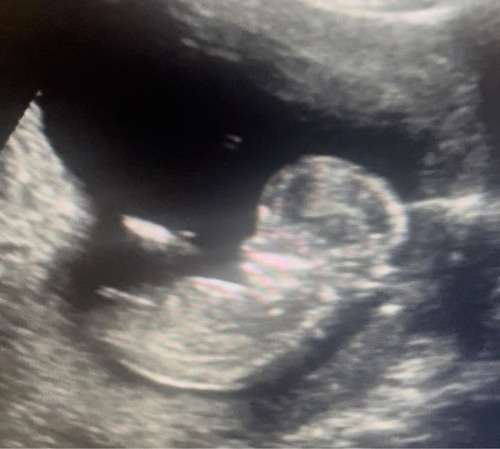

12+6🌸 hoor graag wat jullie denken te zien!

En hier een tweede foto- 12+6 🌸

Meisje denk ik